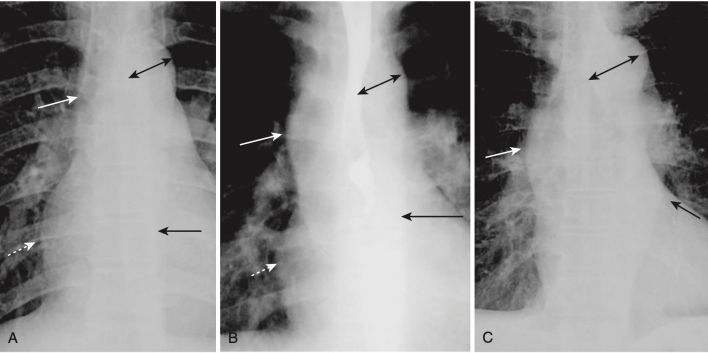

- Thông thường, động mạch chủ dưới song song với cột sống và hầu như không thể nhìn thấy trên phim chụp X quang ngực thẳng. Khi động mạch ngoằn ngoèo, nó sẽ lệch ra xa cột sống ngực về phía bên trái của bệnh nhân (Hình 3).